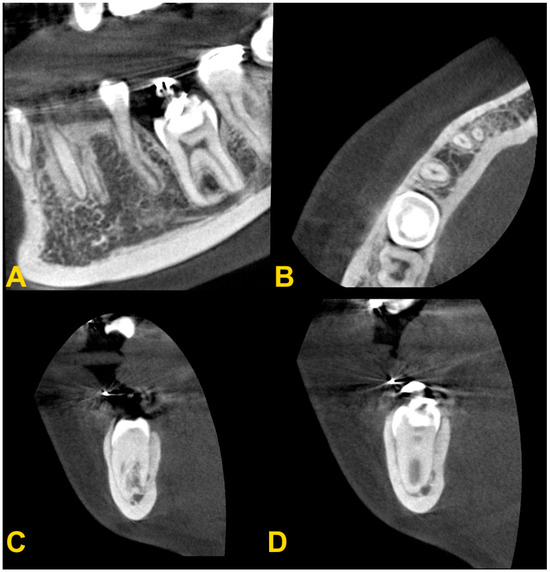

Figure 4.

Cone-beam computed tomography examination of tooth no. 36 with infraocclusion: (A) panoramic reconstruction, (B) axial view, (C) transectal view through the mesial root, and (D) transectal view through the distal root (the same patient as in Figure 6D).

Intraoral photography: (A) mild reinclusion of tooth no. 85 in the presence of a permanent successor—the patient requires observation; (B) moderate reinclusion of teeth nos. 55 and 85 in the absence of permanent successors, and presence of lateral open bite—the teeth require extraction; (C) severe reinclusion of tooth no. 75 in the presence of permanent successor (the same patient as in Figure 3C)—the tooth requires extraction; and (D) infraocclusion within the permanent dentition—tooth no. 36—the tooth should be removed (the same patient as in Figure 4).